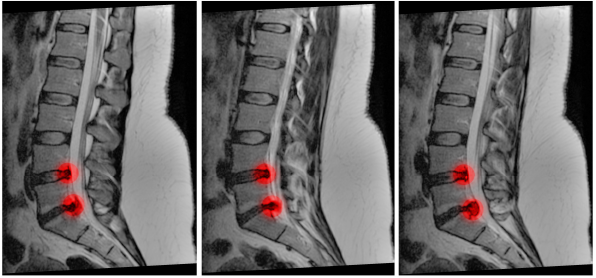

CAUDA EQUINA

RARE

MOST COMMON: central disc prolapse (usually L4/5 OR L5/S1)

OTHER: tumors / infections (abcess,disctitis) / trauma / haematoma

low back pain / bilateral sciatica (50% of cases) / reduced sensation in the perianal area / incontinence (late sign : indicates irreversible damage) / decreased anal tone (good practice to check, however this is not done in primary care)

Urgent MRI

surgical decompression (followed by tests and investigations)